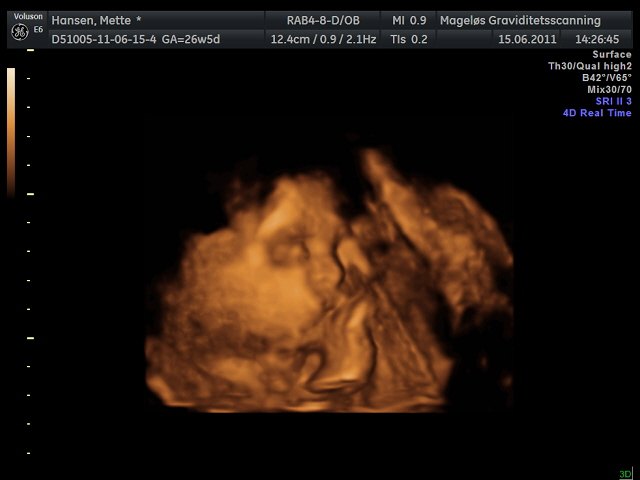

Mettefpigen

Hvor er de flotte de billeder i har lagt ind

Her er det min lille dreng  Han ville selvfølgelig ikk vise hele sit ansigt så har kun fået "noget" af det

Hihi men fik faktisk også et billede af hans dutti, så nu er vi 100% sikker på at det er en dreng  haha.. Så har vi det først billede til hans konfirmation

Vedhæftede fotos (klik for at se i fuld størrelse)